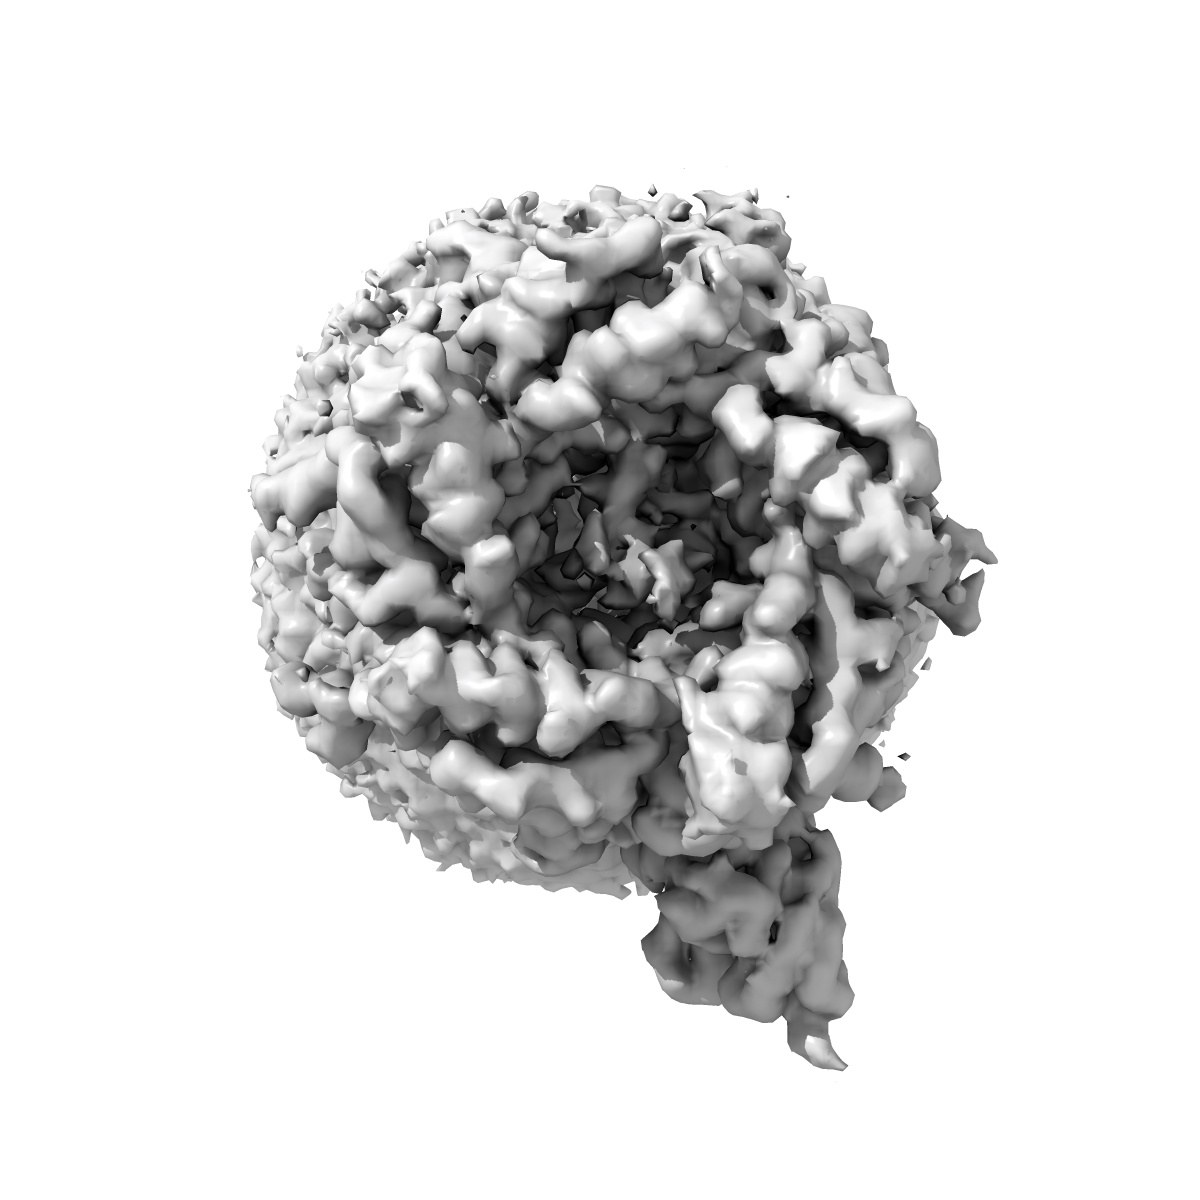

Cryo-EM structure of the alpha1beta3gamma2 GABA(A) receptor in complex with GABA and Nb38 in the short-lived asymmetric open1 state